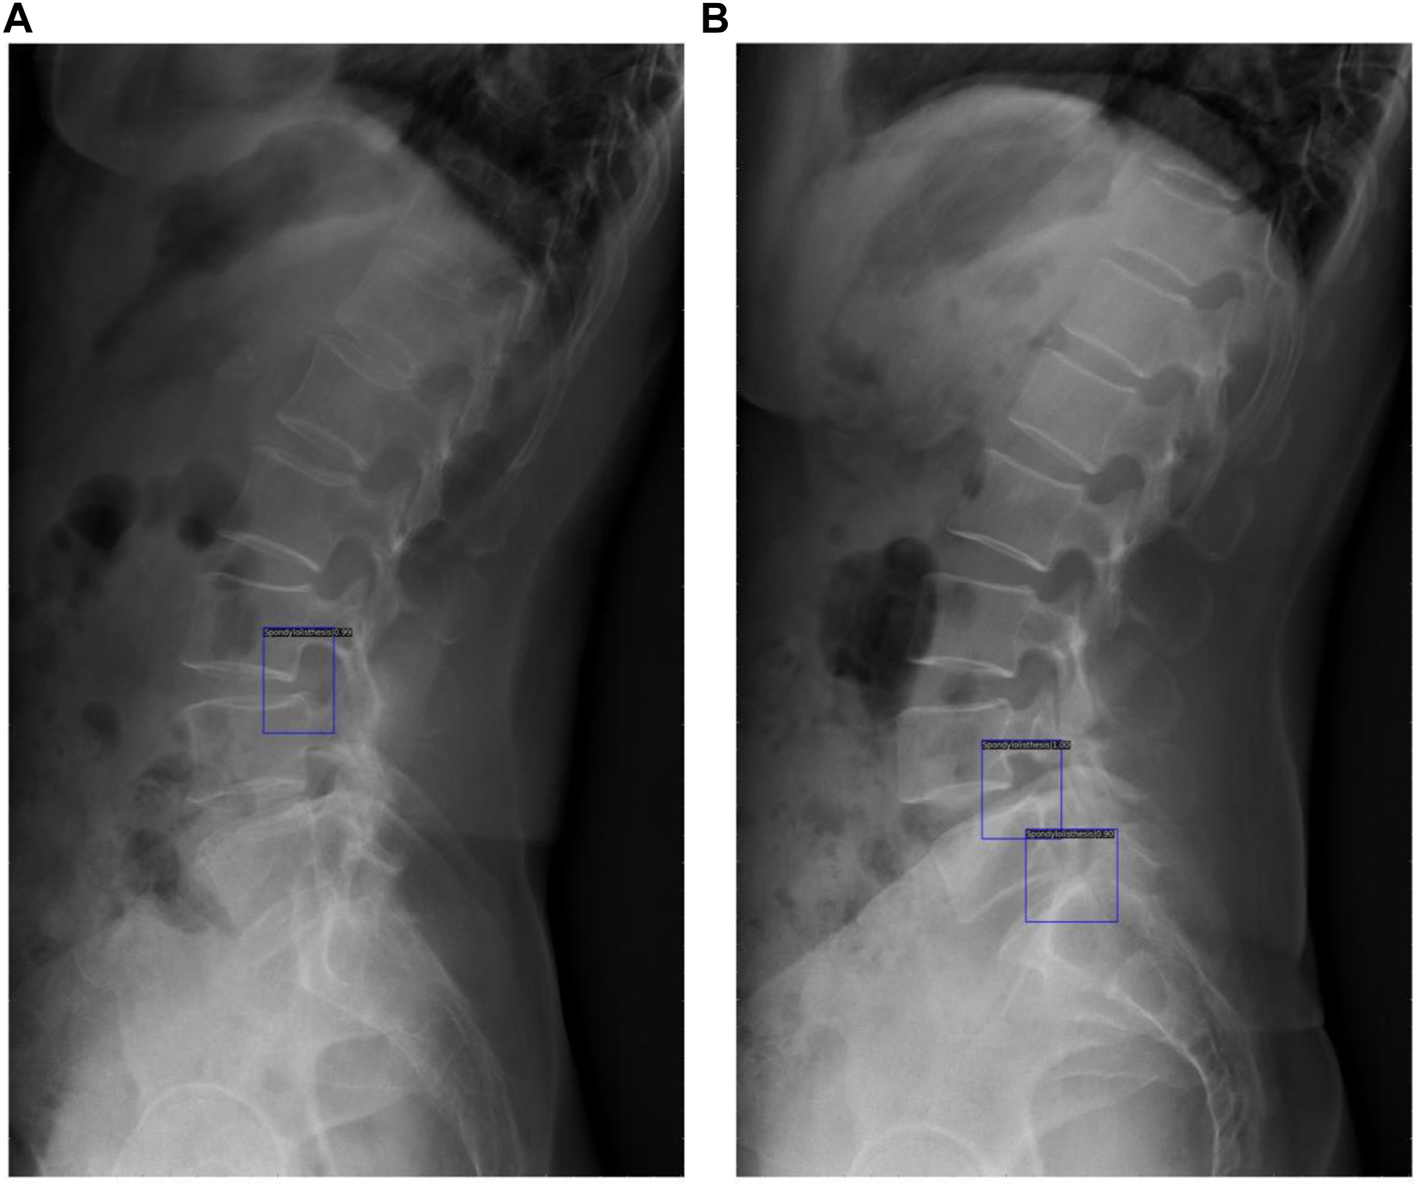

The original image was imported into the AI model and the model automatically executed the entire procedure and produced results with position markers and spondylolisthesis probability of spondylolisthesis (Figure 6). The time from importing a plain film to generating final results took approximately 0.167 s/piece on average, while the average time the doctors group took was about 25.452 s/piece under the same testing data set.

FIGURE 6

These results demonstrated the potential of clinical application of the DL model, with blue rectangles marking the location of spondylolisthesis and numbers showing the probability of spondylolisthesis (A) shows detection of one spondylolisthesis and (B) shows detection of two spondylolisthesis.